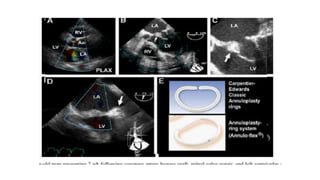

PROSTHETIC VALVE ENDOCARDITIS

• Prosthetic valve dehiscence is highly suggestive of IE.

• Dehiscence can be the only manifestation of IE with a prosthetic

valve in the absence of vegetation or abscess

• A valve rocking motion may indicate valve dehiscence.

• Paravalvular regurgitation may also indicate prosthetic valve

endocarditis but should be compared with any prior paravalvular

regurgitation

• TEE solves this problem for mitral prostheses and improves it for

aortic prostheses .However, when both mitral and aortic prostheses

are present, the mitral device tends to obscure the aortic valve.

Tricuspid and pulmonic devices pose similar problems.

• 30.

PROSTHETIC VALVE ENDOCARDITIS •Prosthetic valve dehiscence is highly suggestive of IE. • Dehiscence can be the only manifestation of IE with a prosthetic valve in the absence of vegetation or abscess • A valve rocking motion may indicate valve dehiscence. • Paravalvular regurgitation may also indicate prosthetic valve endocarditis but should be compared with any prior paravalvular regurgitation • TEE solves this problem for mitral prostheses and improves it for aortic prostheses .However, when both mitral and aortic prostheses are present, the mitral device tends to obscure the aortic valve. Tricuspid and pulmonic devices pose similar problems.